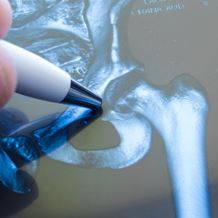

The hip is the largest weight bearing joint in the body and can be affected by a wide range of conditions that cause pain, stiffness, limping and discomfort.

Responsible for bearing your body weight and allowing a wide range of motion, the hip joint is vulnerable to forms of arthritis either through wear and tear (osteoarthritis), disease (rheumatoid arthritis) or injury, which can include fracture resulting from brittle bones (osteoporosis).

Hip pain can also indicate inflammation of the bursa (bursitis), hip displacement (dysplasia), injury or muscle strain and soft tissue damage. Hip conditions can be diagnosed and treated through examination, imaging and surgery if necessary.